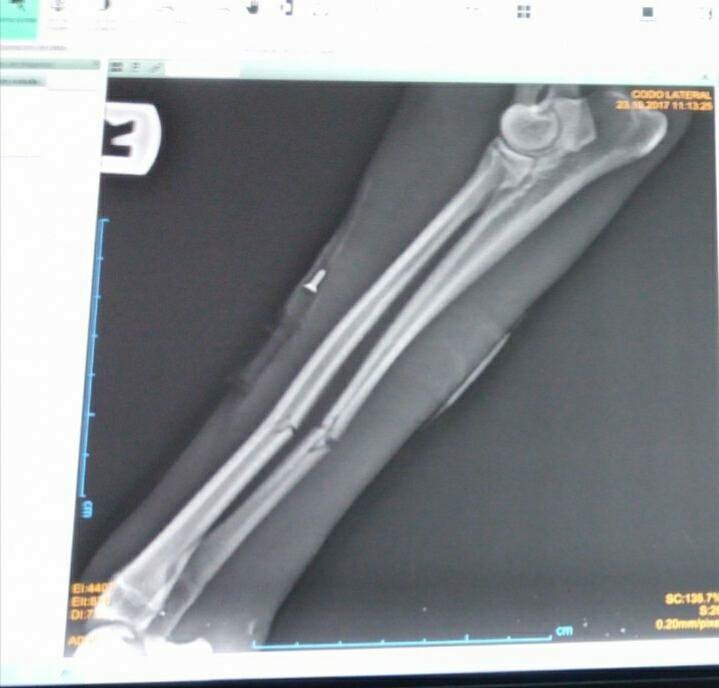

Dieser arme Hund wurde auf einer Straße in Spanien angefahren und einfach liegengelassen. Leider ein alltägliches Bild in Spanien. Zum Glück wurden unsere Tierschützerinnen informiert und haben Osito, wie sie den Rüden genannt haben, gleich in die Tierklinik gefahren. Er wurde geröngt und wird nun in der Klink versorgt. Beide Vorderbeine und einige Rippen sind gebrochen und Osito hat einen Riss im Kopf. Trotz der großen Schmerzen wedelt dieser liebe Hund bei jedem lieben Wort und jeder Streicheleinheit mit seiner Rute. Osito ist ein sehr lieber und geduldiger Patient, der es verdient hat, dass wir ihm helfen. Der Klinkaufenthalt und die nötige Operation kosten ca. 800 €. Unsere Tierschützerinnen benötigen dringend finanzielle Hilfe bei der Deckung der Kosten, die nun anfallen. Vielleicht gibt es ja einige tierliebe Menschen, die sich mit einer, und sei es noch so kleinen, Spende, an der Operation und dem Klinkaufenthalt beteiligen möchten. Jede Spende wird umgehend nach Spanien weitergeleitet. Wir stellen gerne eine Spendenbescehinigung aus. Osito, wir lassen dich nicht im Stich.